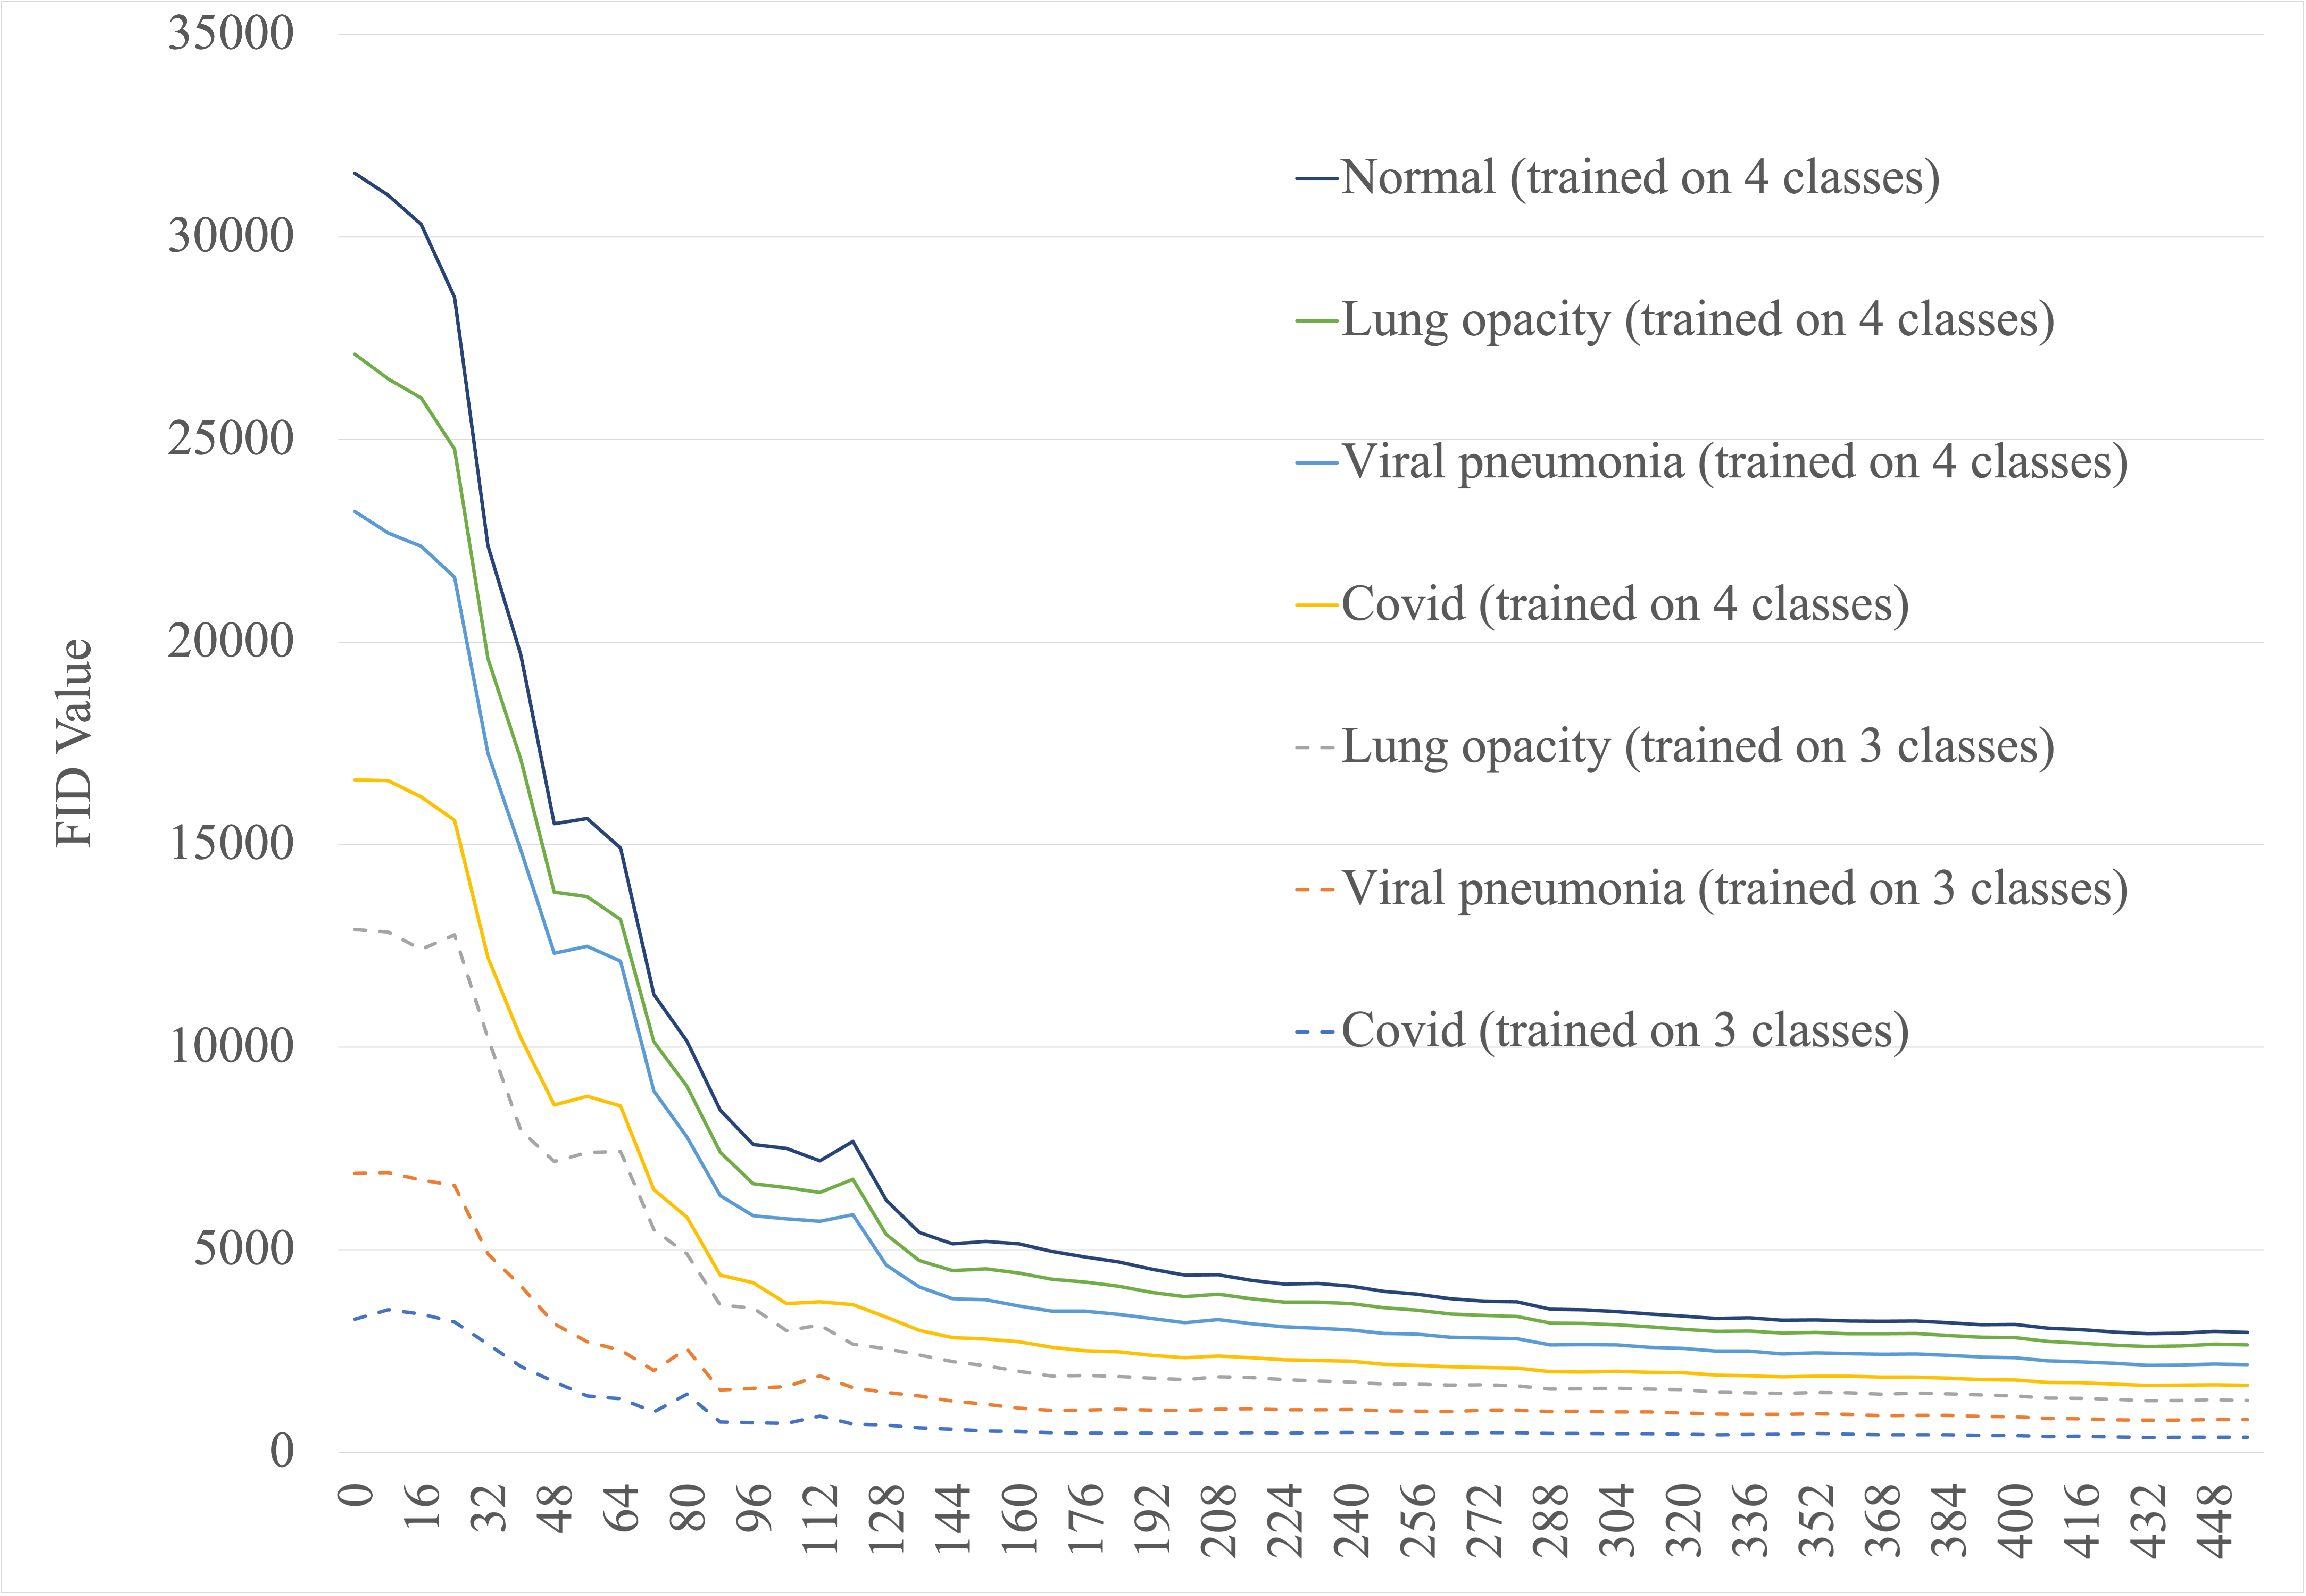

In contrast to classical metrics, the FID compares whole datasets not individual images, as described in Fréchet Inception Distance section. The sensitivity of this metric to image distortions is visualised in Fig. 5 using GAN-generated images from different stages of training (epochs: 16, 96 and 872).

In the presented analysis the official PyTorch StyleGAN2-ADA implementation is used with class-conditional generation enabled. A single model is trained to generate images depending on the selected class label. In the proposed GAN augmentation approach the synthetic images are generated only for underrepresented classes in order to obtain a fully balanced dataset. Therefore the inclusion of the normal (healthy) class of images is not necessary for the GAN training. Nevertheless, two scenarios are analysed to verify if providing additional images with similar overall spatial features is beneficial: GAN training on 3 classes of images and on 4 classes of images. In both cases training time is observed to be similar.

To eliminate overfitting, image quality is monitored throughout the training process. The Fréchet Inception Distance is calculated every epoch for each image class independently between generated and real data samples. It is evaluated on the training subsample (Dataset) as the FID metric is known to be biased for small datasets Karras et al. (2019). In addition, the quality of generated images is verified by calculating RMSE, SRE and SSIM metrics. The training process is stopped when discriminator overfitting appears and the quality of generated images starts to decrease. The epoch that corresponds to the smallest mean FID metric from all image classes is selected as a base for the GAN augmentation network.

The training process of the GAN model is monitored with the FID metric presented in Fig. 8. It is seen that the decrease of FID has reached a plateau for all simultaneously trained classes and the model has learned the characteristics of each of the samples. It is also seen that including in the training a data set with an additional class (a scenario with four classes including a normal sample), which introduces a large imbalance of the samples, leads to poorer performance of the model. Final FID values calculated between original and generated samples are presented in Table 1 together with values calculated between COVID-19 and the other three classes. It can be observed that the FID values are significantly lower, thus the images are more similar, for generated samples than those obtained between the four classes. Visual comparison of exemplary generated COVID-19 images to real ones is presented in Fig. 9.